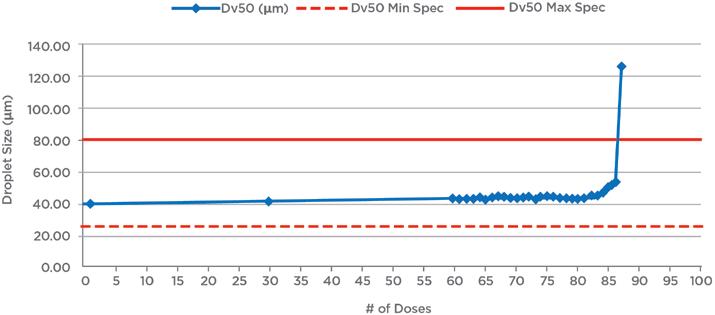

ARCUS®: a Commercialised Technology Enabling High-Dose, Highly Respirable Powders

Alan Watts, Director of Innovation & Partnerships for Orally Inhaled Products

Catalent

Michael Tauber, Senior Director of Pharmaceutical Development

Acorda Therapeutics

High-Dose Delivery Platform for Crystalline DPIs